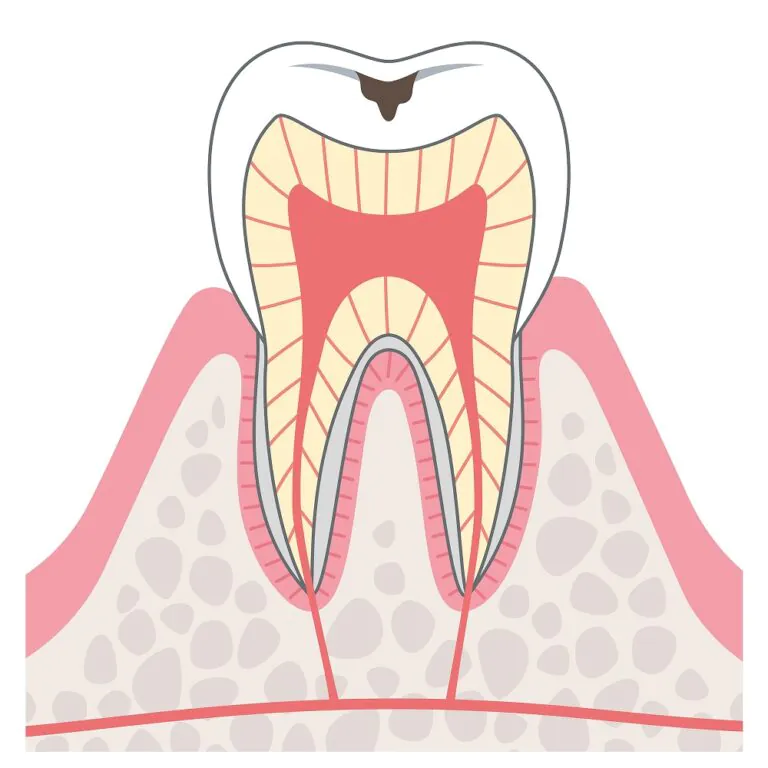

C0:ケアの見直しで改善する見込みあり

歯の表面を覆うエナメル質が溶かされてツヤが失われ、白く濁ったり茶色くなったりする段階です。歯そのものは溶かされていないため、痛みやしみるといった症状はありません。

C1:小さなむし歯

歯の表面が溶けて、ごく小さな穴があいている状態です。痛みやしみるなどの症状はまだ現れず、患部が黒くなる程度に留まります。

C2:痛みやしみるなどの症状が現れる

むし歯が歯の内部の象牙質にまで達した状態です。歯の黒い範囲が広くなるとともに、痛みやしみるなどの症状が現れます。進行すればするほどに歯の神経に近くなるため、それだけ症状が現れやすくなります。

C3:激しい痛みが生じるむし歯

むし歯が歯の神経に達した状態です。強い炎症が起きて激しい痛みが生じるため、この段階で歯医者に駆け込む方が少なくありません。

C4:歯の根だけが残った状態

歯の大部分が溶かされて、歯の根だけが残った状態です。歯の神経が壊死しているため、痛みは消失します。

しかし、歯の根の中で細菌感染が生じ、再び痛み出すことがあります。